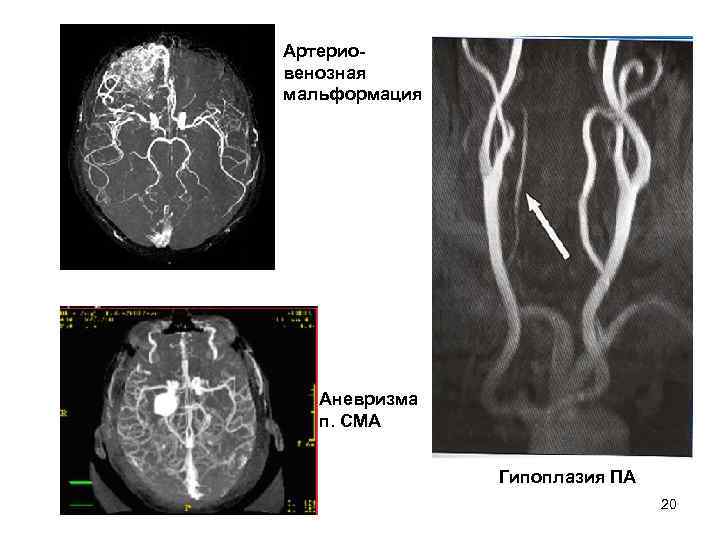

МР-ангиография Магнитно-резонансная ангиография (МРА) — метод получения изображения сосудов при помощи магнитно- резонансного томографа. Исследование проводится на томографах с напряжённостью магнитного поля не менее 0, 3 (GE Brivo MR 235) Тесла. Метод позволяет оценивать как анатомические, так и функциональные особенности кровотока. МРА основана на отличии сигнала подвижной ткани (крови) от окружающих неподвижных тканей, что позволяет получать изображения сосудов без использования каких-либо рентгеноконтрастных средств. Для получения более чёткого изображения применяются особые контрастные вещества на основе парамагнетиков (гадолиний).

• Магнитно-резонансная ангиография (МРА) • на томографах с напряжённостью магнитного поля > 1. 0 Тесла – отличие сигнала подвижной ткани (крови) от окружающих неподвижных тканей – анатомические, функциональные особенности МК • без использования рентгенконтрастных веществ • четкое изображение - вещества на основе парамагнетиков - гадолиний 19

Артерио- венозная мальформация Аневризма п. СМА Гипоплазия ПА 20